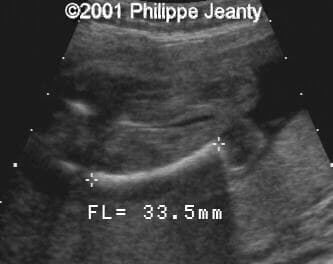

and a longitudinal view of both lower legs:

image39

image38